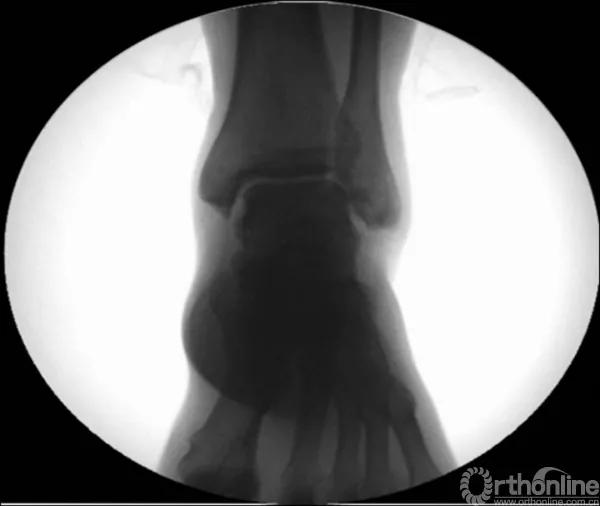

X线诊断:标准的踝关节影像学评估应包括3个位相:前后位(图5),踝穴位(内旋15°)(图6),侧位(图7)。

当踝关节严重损伤时内外踝及距骨将发生不同程度的移位(图8)。有时外踝骨折会伴有三角韧带的损伤,静态的X线摄片并不能准确地反映踝关节的稳定性,应力位片及MRI检查可完善对踝关节稳定性及韧带损伤的评估(图9)。此时应通过患肢损伤机制及放射资料准确判断踝关节损伤的类型以正确指导复位和固定。有时单纯内踝骨折可能是更为复杂的“Maisonneuve骨折”的一部分,该骨折还包括腓骨近端骨折及韧带联合损伤,故X线检查应投照整个胫腓骨。

图8 骨折移位明显合并有脱位